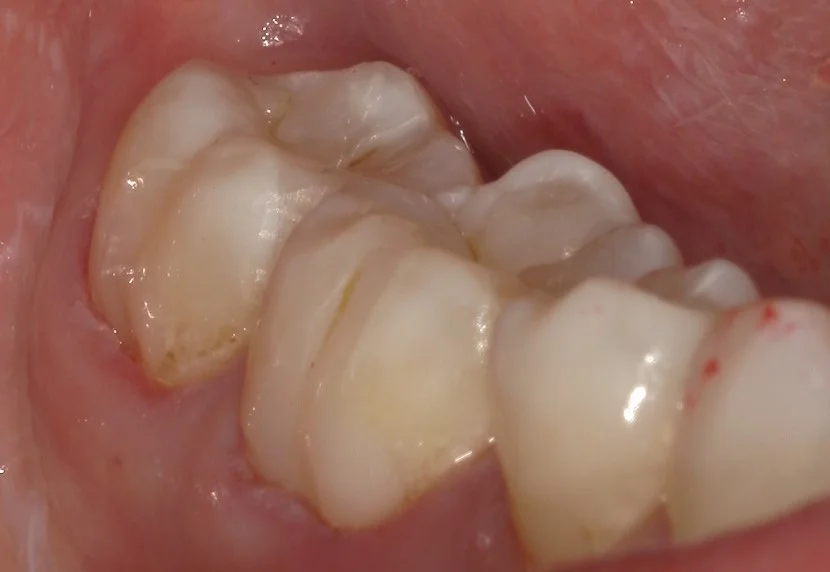

そして詰め終わったのがこちらです。

根元の方が分かりやすい角度でも写真を撮らせてもらいました。

一切の段差なく綺麗に詰まっているのが分かるかと思います。